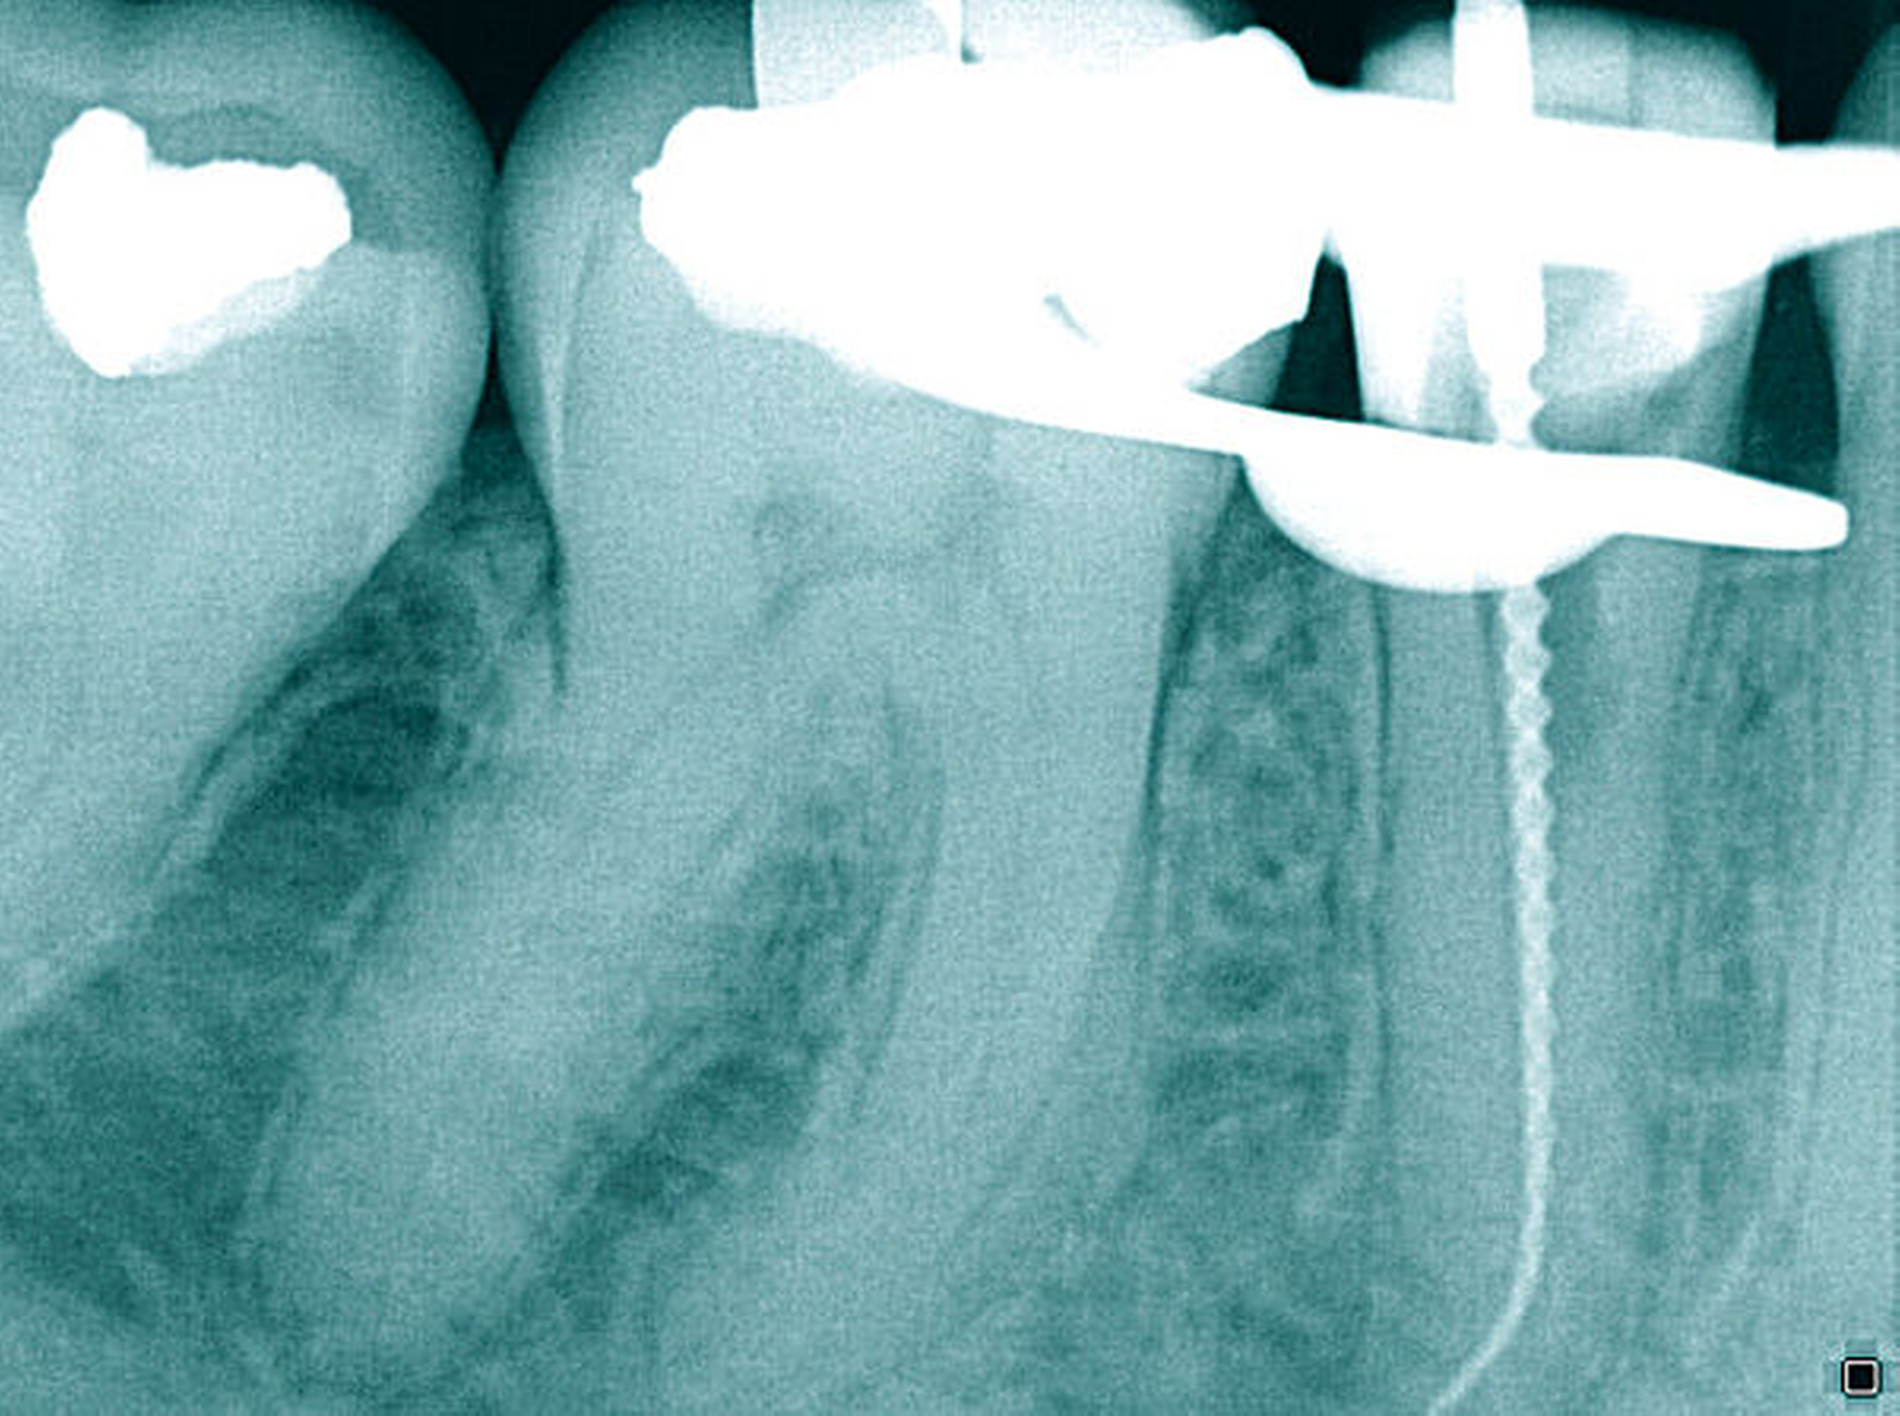

Der Patient stellte sich mit rezidivierenden Beschwerden am Zahn 45 nach einer vor Jahren abgeschlossenen Wurzelkanalbehandlung vor. Die Allgemeinanamnese war unauffällig. Die Schmerzsymptomatik ließ sich auf den Zahn 45 bei positivem Perkussionsreiz lokalisieren. Der approximale Kontaktpunkt distal zum Zahn 46 fehlte. Distal fiel ein pathologischer Sondierungswert von 4 mm auf. Eine Blutung ließ sich bei passiver Messung auslösen und begründete eine plaqueinduzierte Gingivitis.

Auf der intraoralen Röntgenaufnahme lagen eine unvollständige Wurzelkanalfüllung und eine apikale Aufhellung am Zahn 45 vor. Apikal ist auf der Röntgenaufnahme kein Wurzelkanal erkennbar. Die zu kurze Wurzelkanalfüllung deutete auf eine apikale Blockade von eingepresstem Debris oder eine Stufenpräparation hin (Abbildung 14). Als seltene anatomische Variation war eine apikale Aufteilung in zwei Wurzelkanäle in Betracht zu ziehen, so dass die Nutzung einer optischen Vergrößerung mit koaxialer Lichtzufuhr als Hilfsmittel empfehlenswert erschien. Die apikale Wurzelkrümmung ließ einen gleichmäßigen großen Krümmungsradius vermuten. Bei lateralen Aufhellungen ist mit einem lateralen Foramen apicale oder einer Wurzelkanalaufteilung zu rechnen, so dass in diesem Fall die apikale Erweiterung und der Verschluss eine sehr hohe Schwierigkeit vermuten lassen.

Die Differenzialdiagnostik und die Therapie unterlagen erwartungsgemäß dem sehr hohen Schwierigkeitsgrad. Es wurde eine dentinadhäsive Aufbaufüllung mit Restauration des fehlenden Kontaktpunkts bei subgingivaler Lage des Füllungsrandes erforderlich und zusätzlich musste die apikale Blockade minimalinvasiv mit modernen endodontischen Hilfsmitteln eliminiert werden. Die Entfernung der alten Wurzelkanalfüllung gelang in der Kombination von Handinstrumenten und rotierenden NiTi-Feilen (Abbildungen 15a und 15b). Unter Sicht mit dem Dentalmikroskop konnte die intrakanaläre Blockade mit Ultraschall und vorgebogenen Feilen überwunden und thermoplastisch verschlossen werden, so dass bereits sechs Monate nach Therapieabschluss die apikale Aufhellung und klinische Schmerzsymptomatik abgeklungen waren (Abbildung 15c).